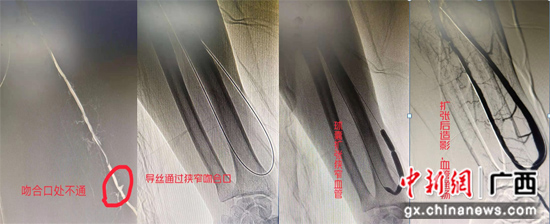

上图造影可见自体消息脉吻合口不通,显影只见残端,用导丝通过吻合口,再用球囊依次扩张,扩张进程可见吻合口及血管有明明狭窄,扩张后造影可见血管通畅,可触及自体消息脉内瘘博动及震颤。南溪山医院供图